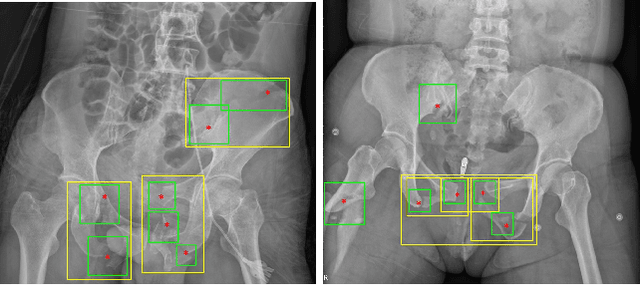

Abstract:Object detection methods are widely adopted for computer-aided diagnosis using medical images. Anomalous findings are usually treated as objects that are described by bounding boxes. Yet, many pathological findings, e.g., bone fractures, cannot be clearly defined by bounding boxes, owing to considerable instance, shape and boundary ambiguities. This makes bounding box annotations, and their associated losses, highly ill-suited. In this work, we propose a new bone fracture detection method for X-ray images, based on a labor effective and flexible annotation scheme suitable for abnormal findings with no clear object-level spatial extents or boundaries. Our method employs a simple, intuitive, and informative point-based annotation protocol to mark localized pathology information. To address the uncertainty in the fracture scales annotated via point(s), we convert the annotations into pixel-wise supervision that uses lower and upper bounds with positive, negative, and uncertain regions. A novel Window Loss is subsequently proposed to only penalize the predictions outside of the uncertain regions. Our method has been extensively evaluated on 4410 pelvic X-ray images of unique patients. Experiments demonstrate that our method outperforms previous state-of-the-art image classification and object detection baselines by healthy margins, with an AUROC of 0.983 and FROC score of 89.6%.